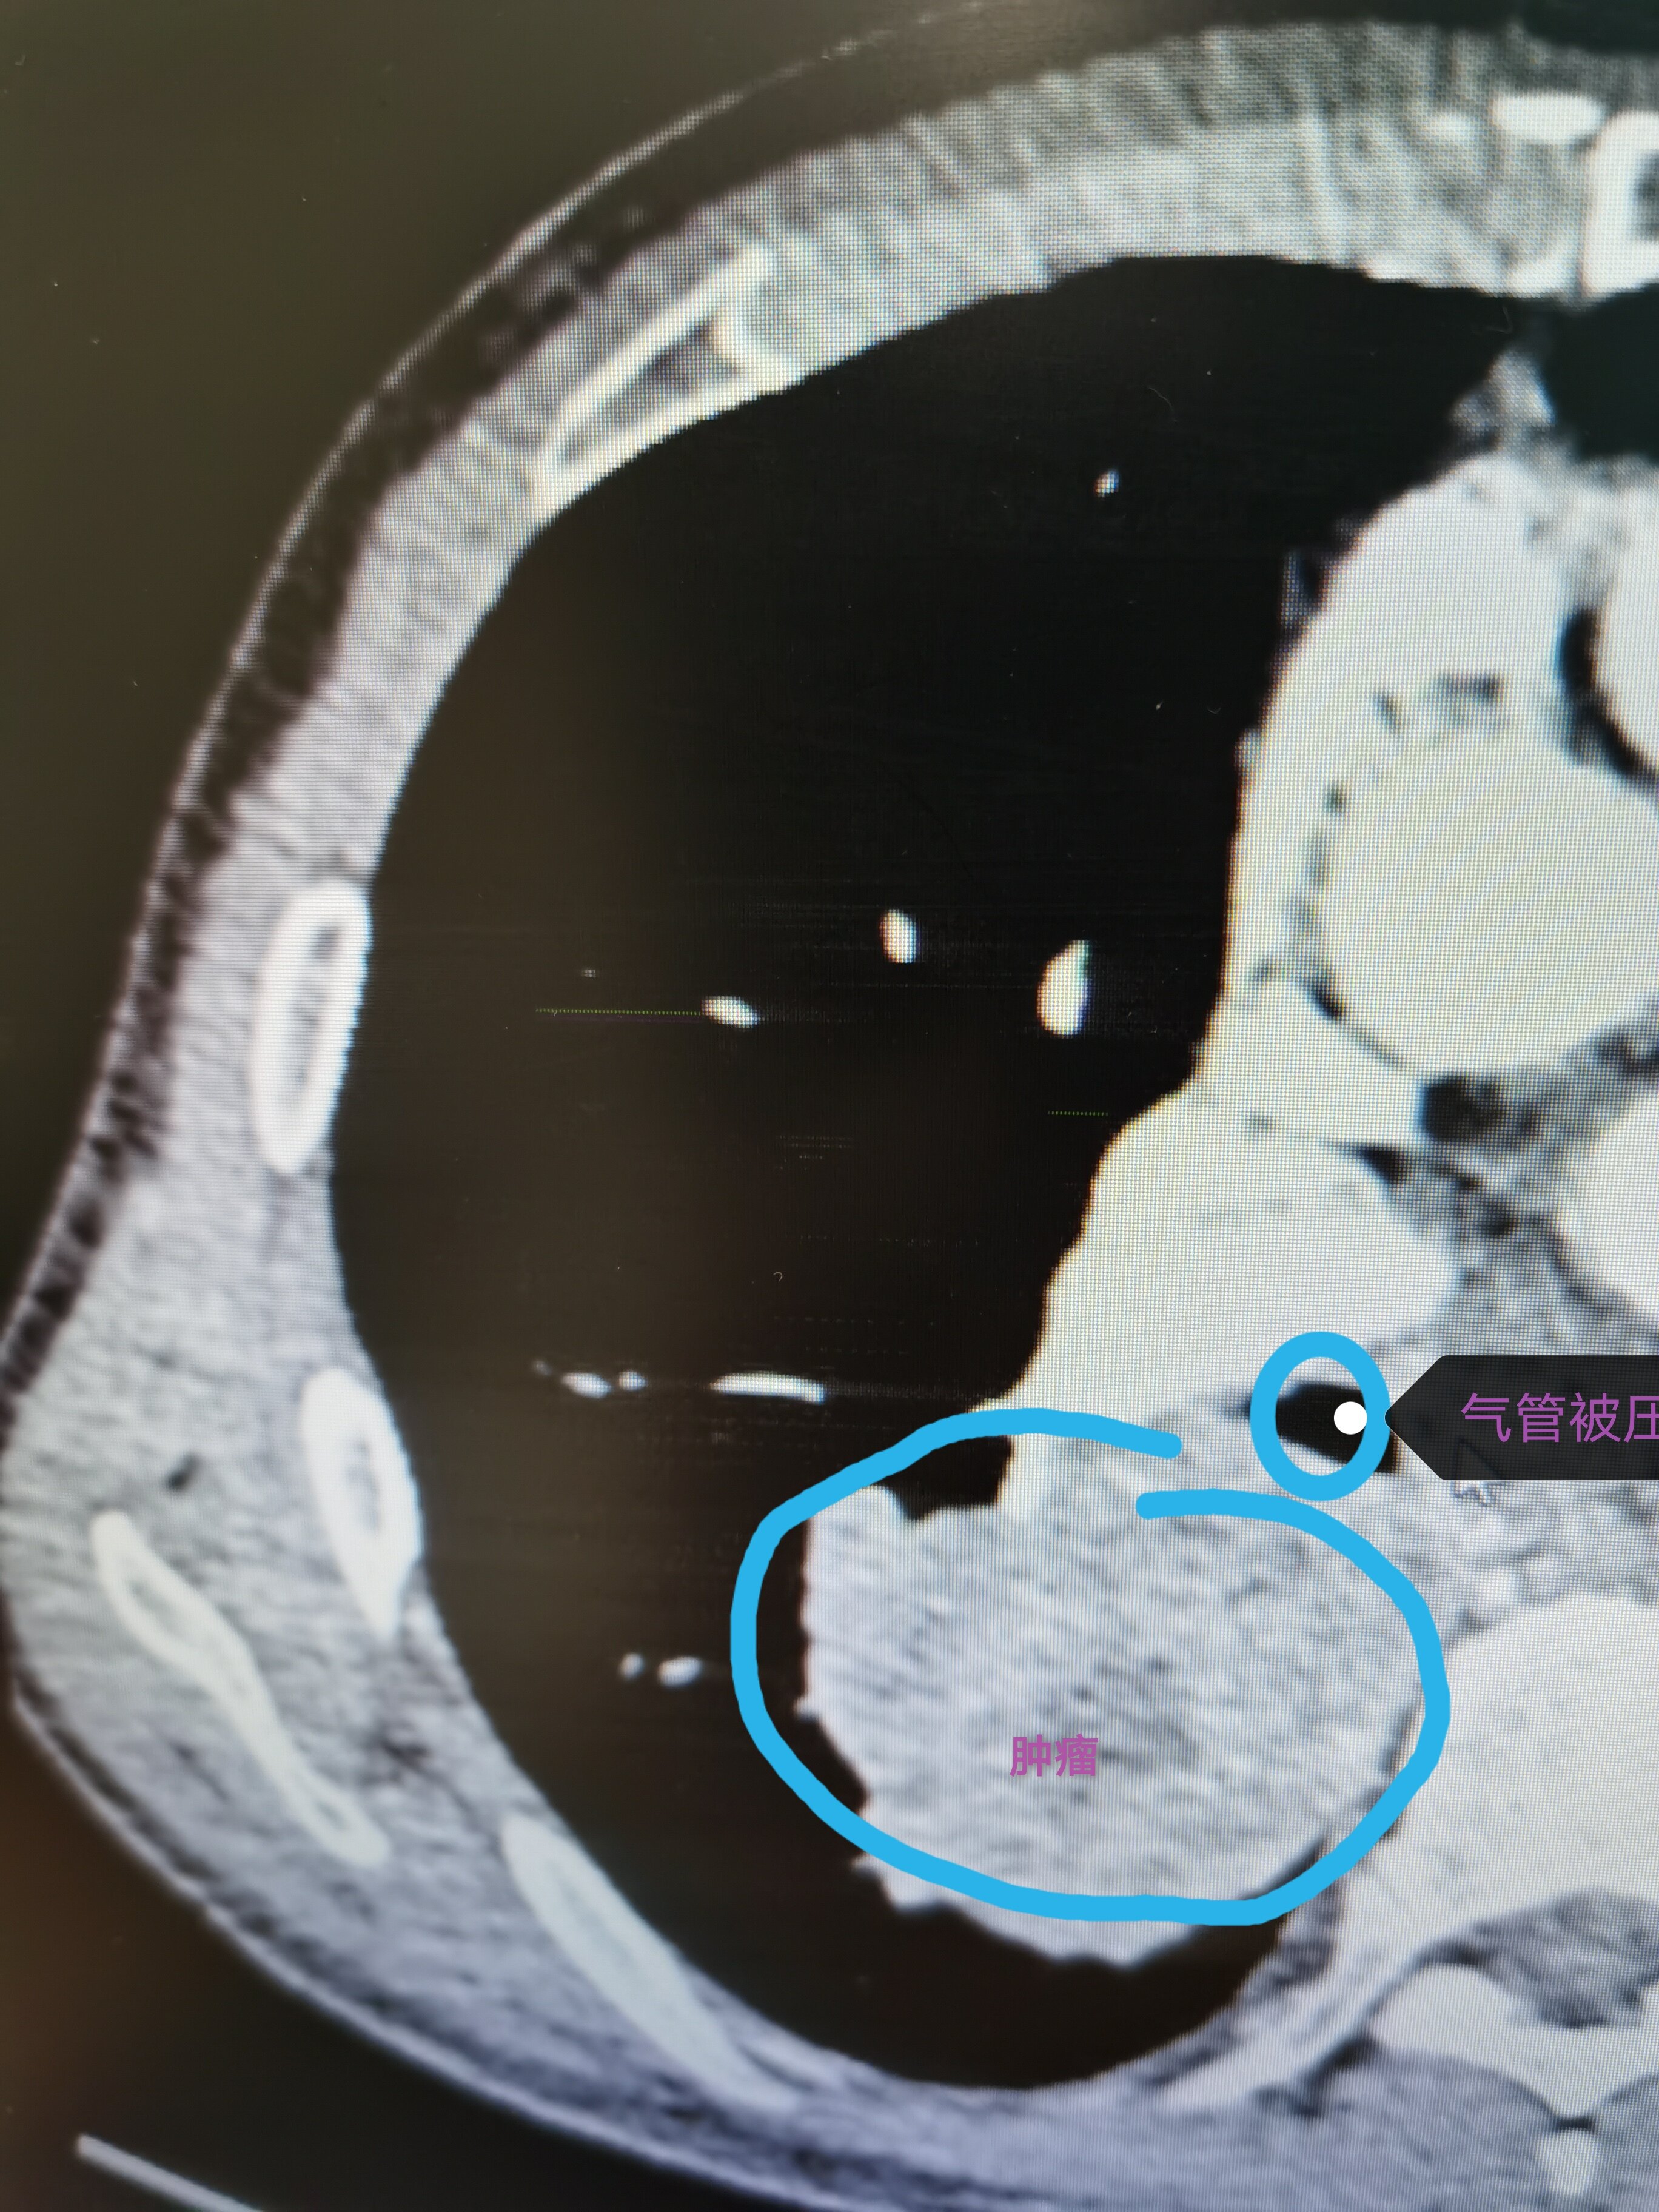

当肿瘤巨大,侵犯主要气管或者侵犯大血管时,并非一定不可以手术,而是可以通过心包内处理血管,这样更加安全避免血管大出血,侵犯气管主干是可以通过气管切除后,再行健康支气管修剪后原位移植,可以保留健康肺组织,避免全肺切除带来的风险和损失。这是我科最近手术的一例典型病例,肿瘤巨大且侵犯主气管,经过切除后原位移植,术后一周后复查CT,移植右上肺愈合良好,患者顺利康复出院